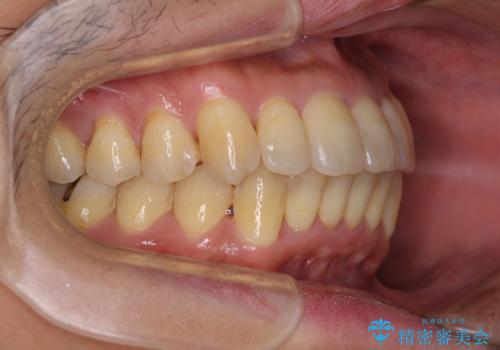

前歯のデコボコ ワイヤー装置での短期間治療

- 1年3ヶ月

治療開始の頃は、食事や歯磨きが慣れず、装置が頻繁に脱落しましたが、2,3ヶ月ほどで慣れ、その後は1年ほどで治療を終えることができました。